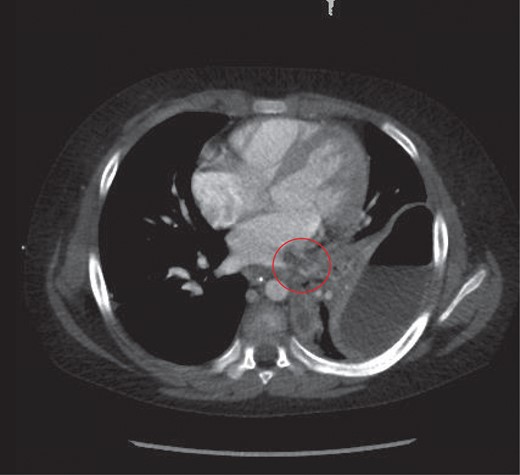

The child underwent a CT scan which demonstrated a large left sided empyema with an air fluid level (Fig. 2). The left lower lobe was collapsed with a multiloculated fluid collection. The appearances were suggestive of a necrotic lung abscess. The suggestion was that a Staphylococcus species was the most likely organism to account for the pattern of infection.

Thoracic CT study the next day, which revealed a large left sided lung empyema with an air fluid level. There was further consolidation and collapse within the left lower lobe and a multiloculated fluid collection.

A further finding on the CT was of a large thrombus within the left pulmonary vein extending into the left atrium and a segmental left lower lobar pulmonary embolus (Fig. 3). The left hemidiaphragm was intact. The abdomen and pelvis showed no further source or complication of sepsis.

Thrombus noted in the left pulmonary vein extending into the left atrium.